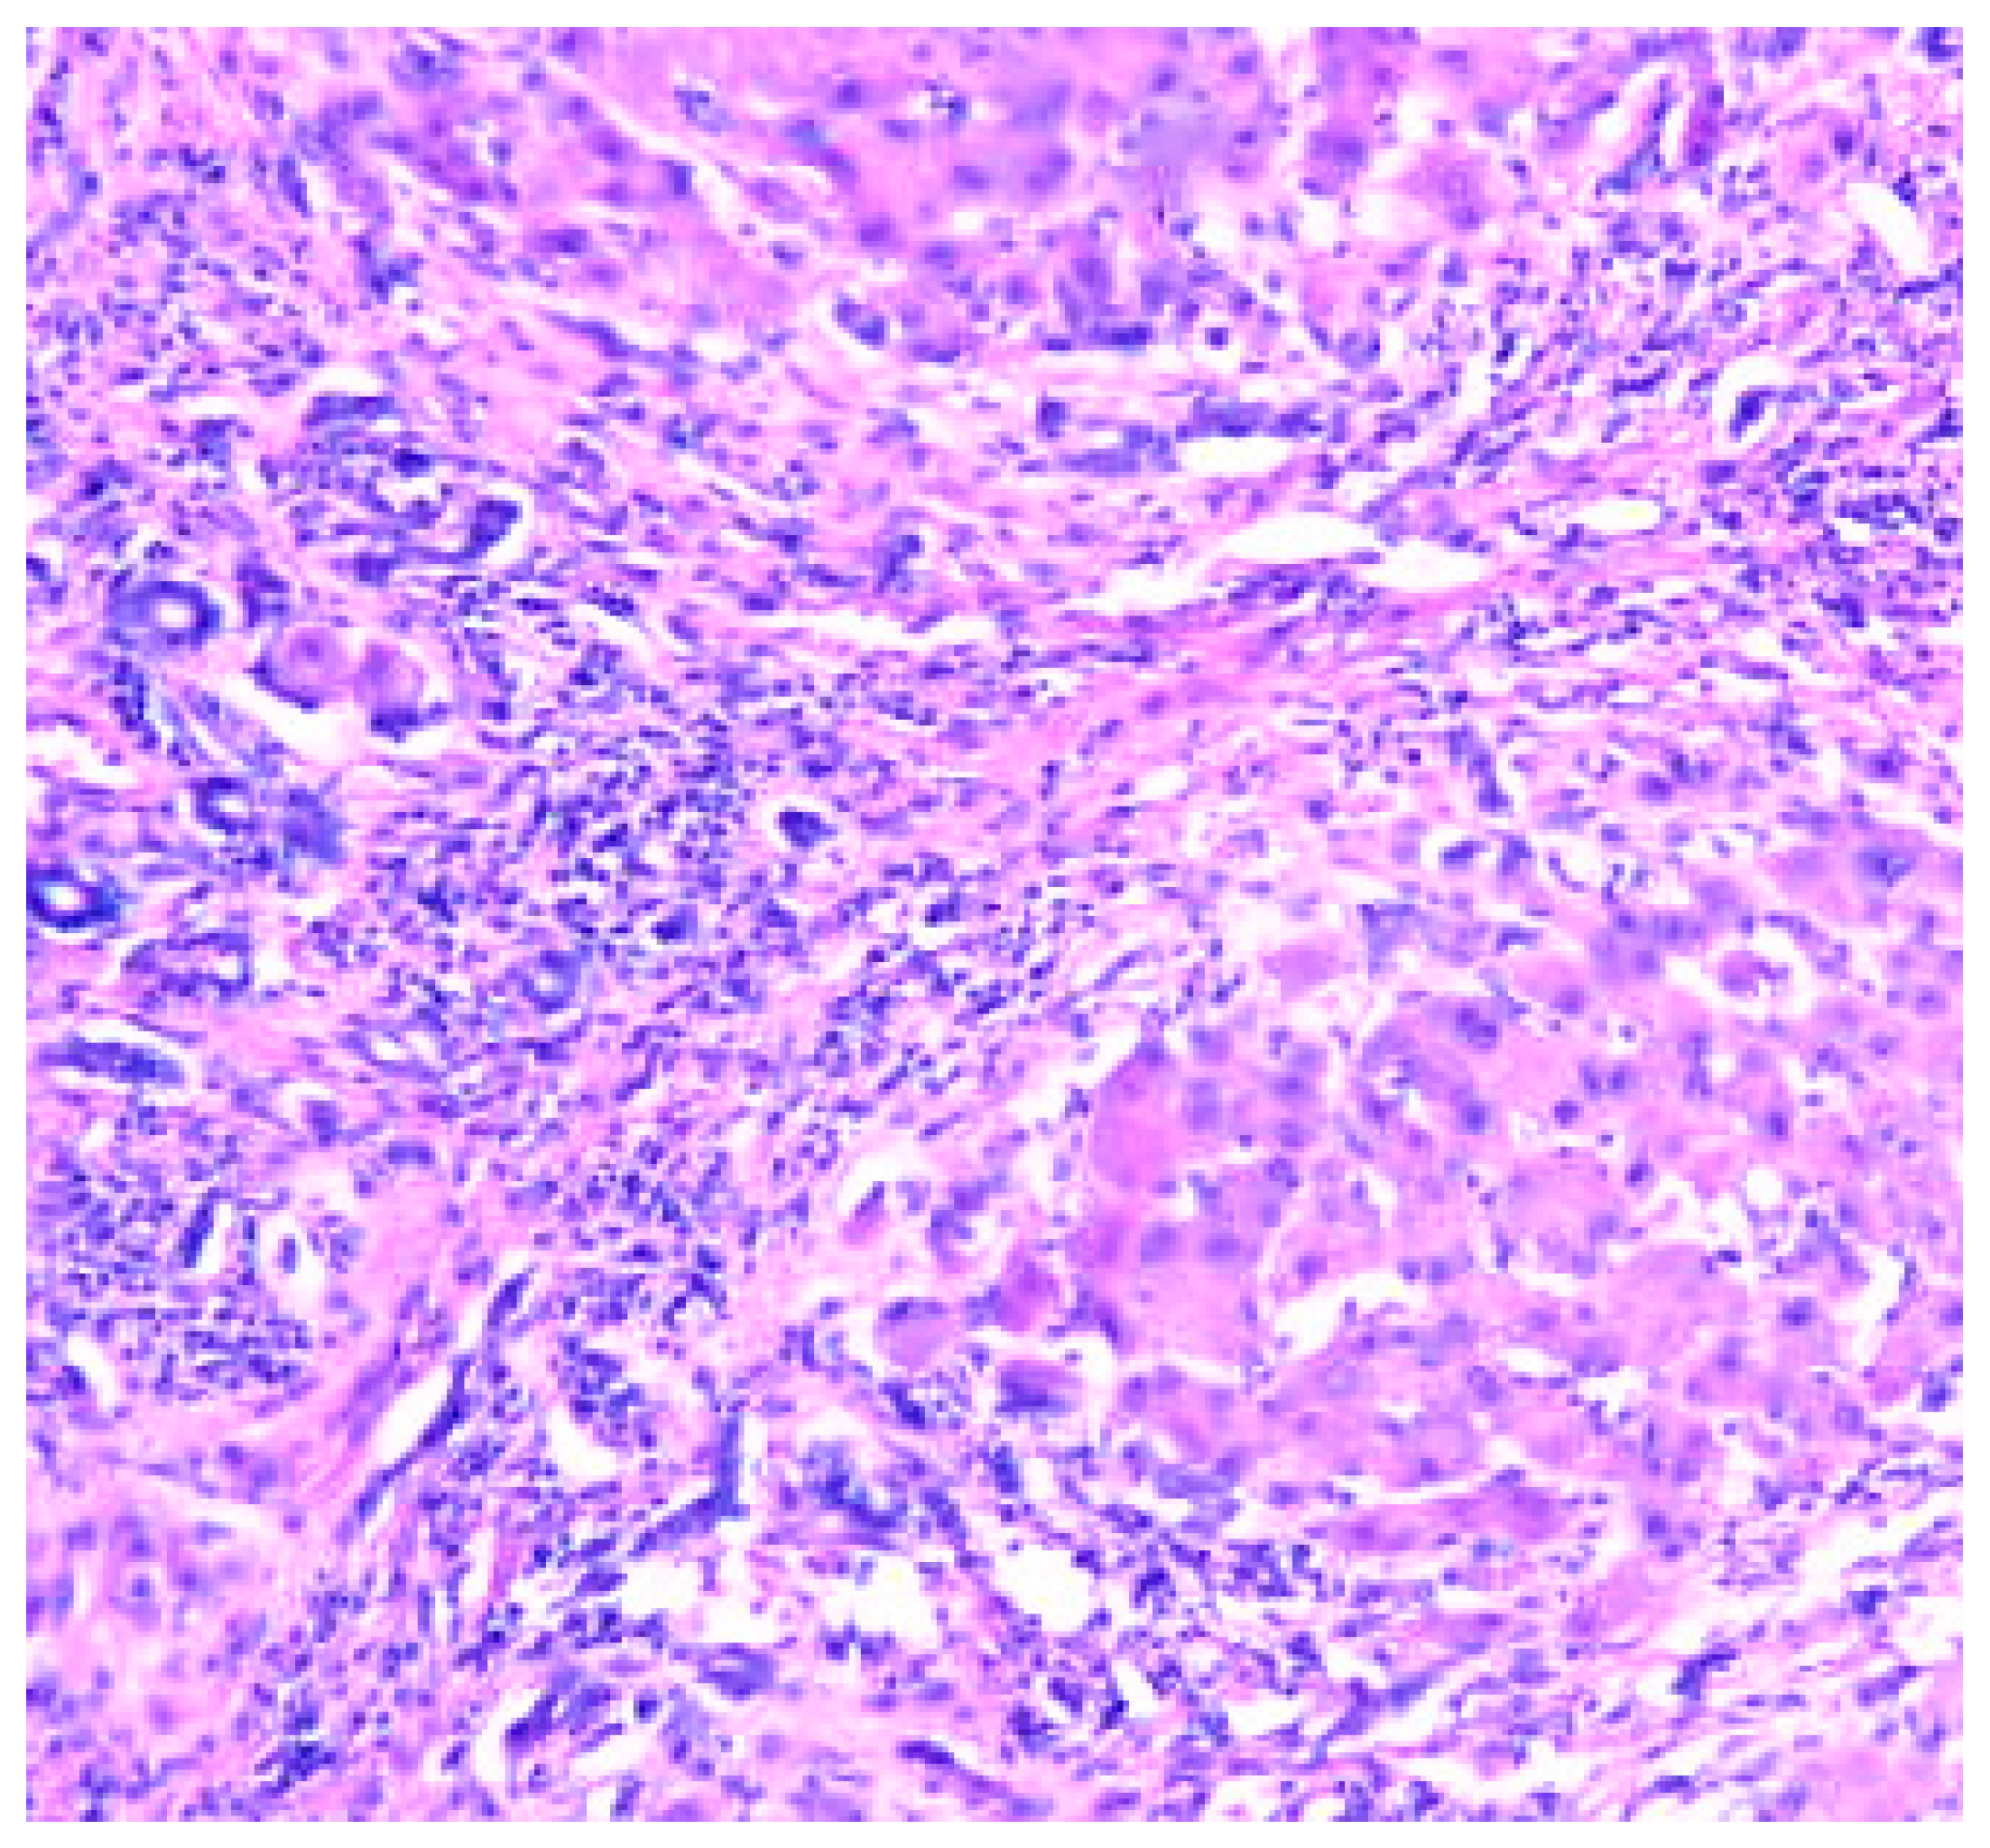

Cirrhosis is a result of continuous liver injury, inflammation, fibrosis, and necrosis. Commonly cause cirrhosis are chronic hepatitis B and C and also life style including alcoholism. The fibrosis present in cirrhosis occurs from the secretion of TGF-beta from the Ito cells in the space of Disse (Figure 3).

Figure 3. Cirrhosis liver x10 H&E stain.